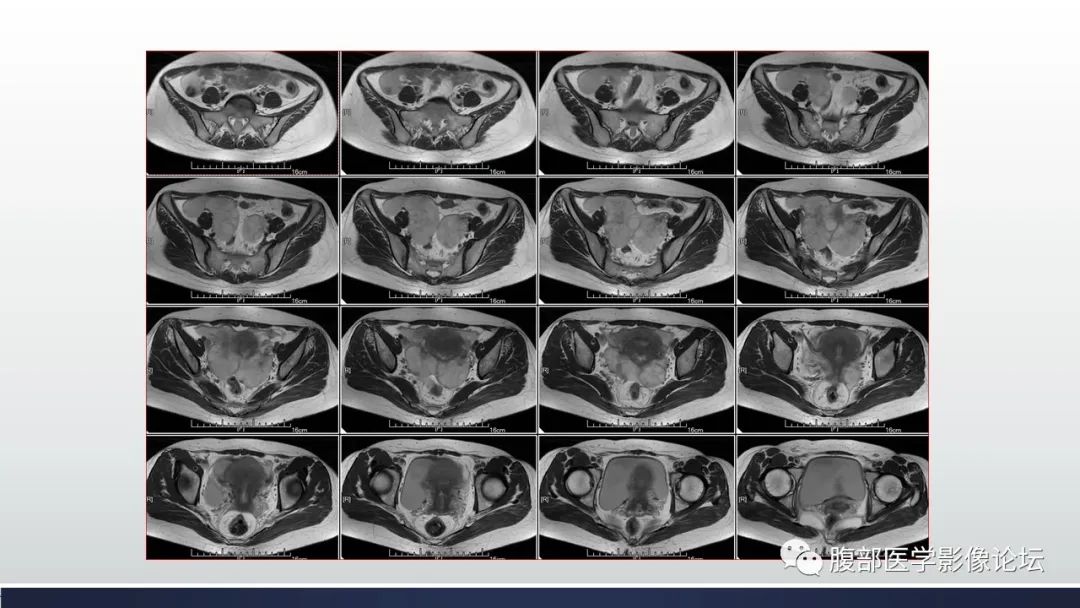

【病例】子宫内膜透明细胞癌1例MR-9

【病例】子宫内膜透明细胞癌1例MR-10

【病例】子宫内膜透明细胞癌1例MR-11

【病例】子宫内膜透明细胞癌1例MR-12